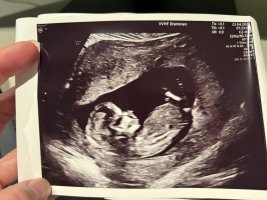

Ser ut som jenta vår, jeg tipper jente

Nub'en pekte ned i uke 12.